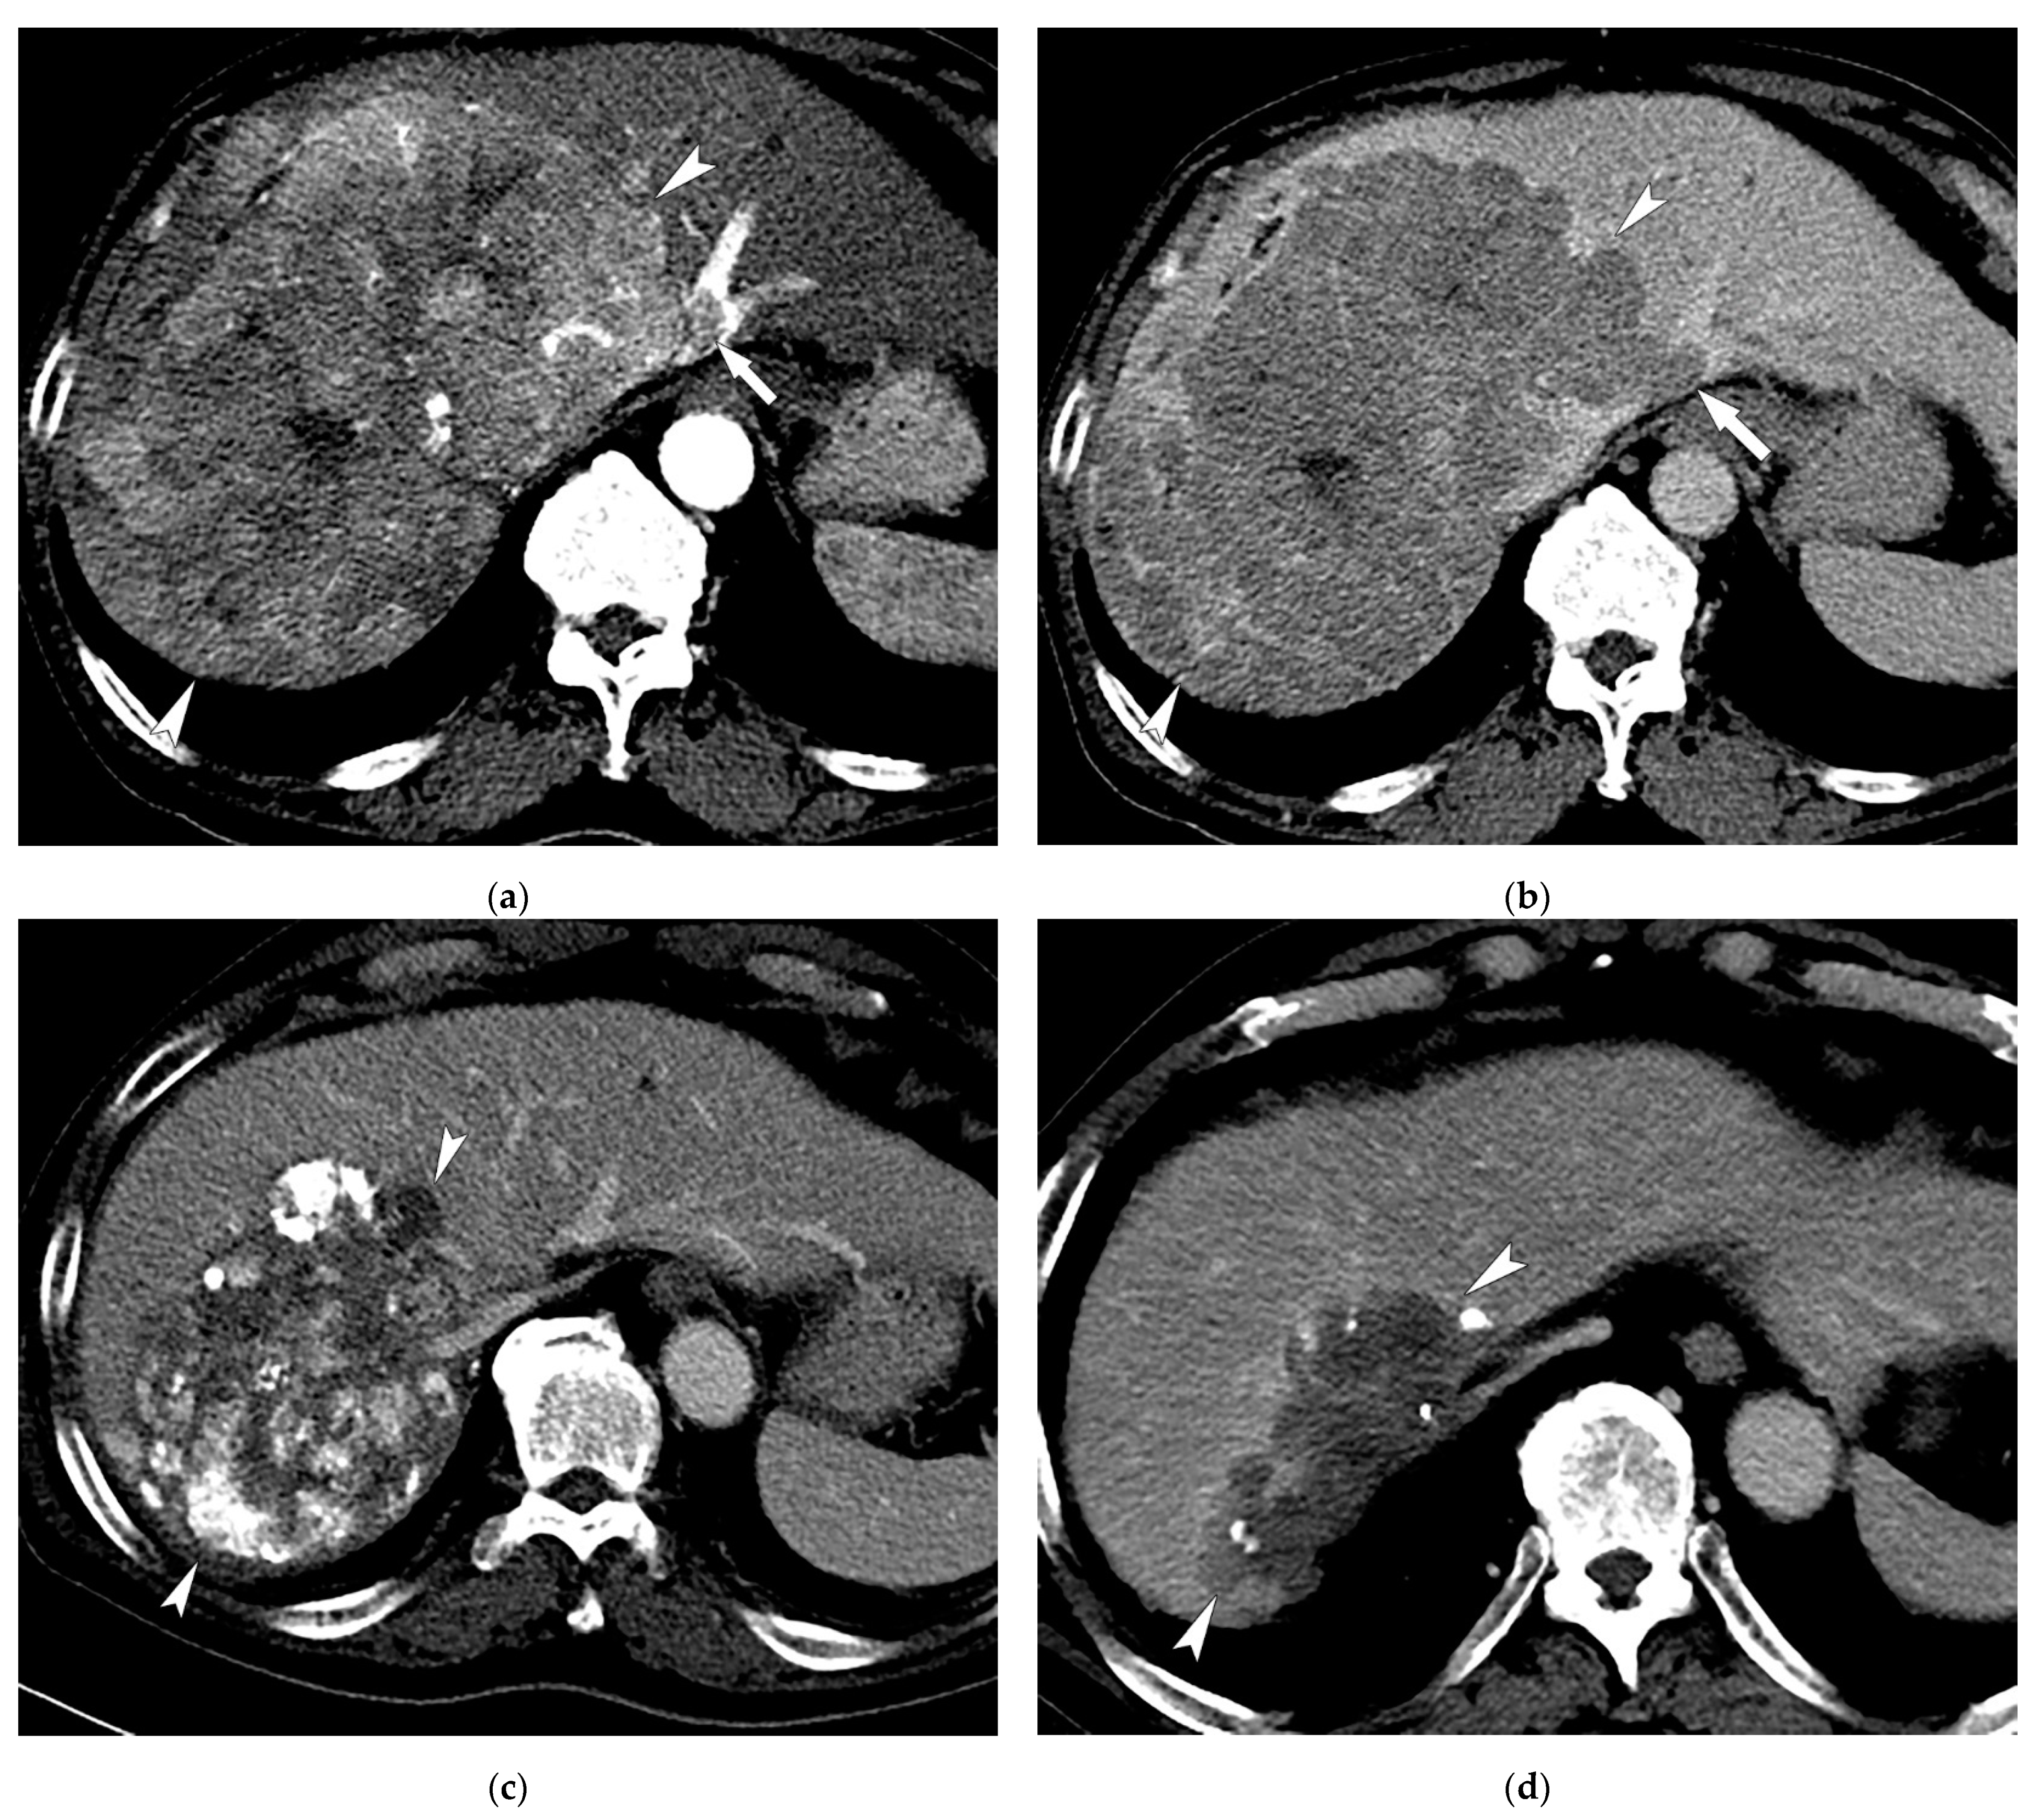

3.2. Radiologic Response after Treatment